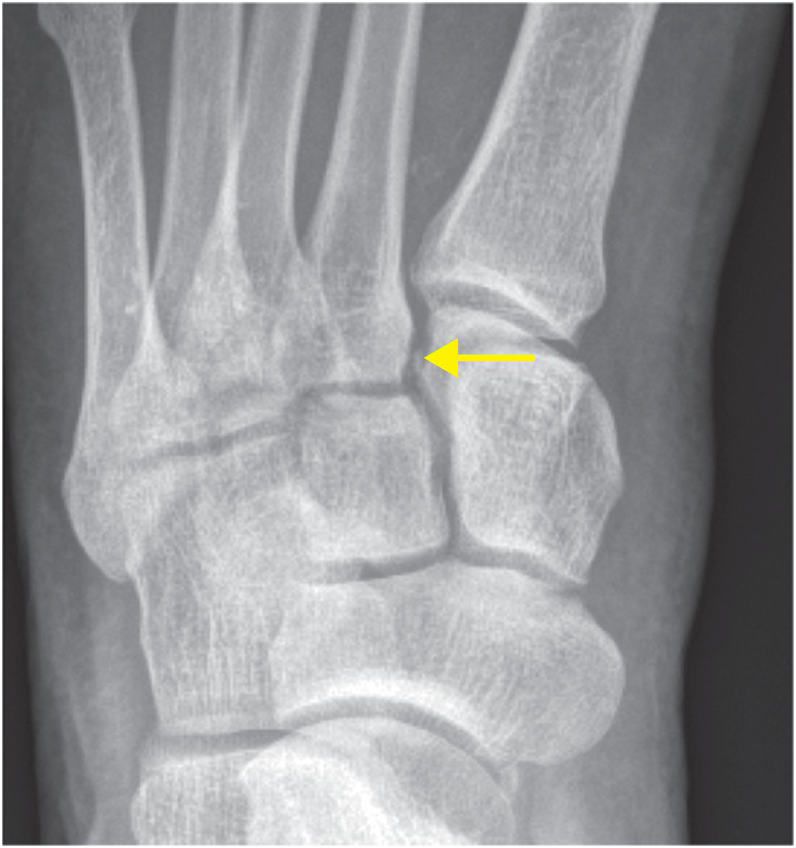

A lisfranc injury is an injury to the ligaments that connect the bones of the midfoot and forefoot. Learn how to identify the lisfranc ligament complex and the bifurcate ligament on mri. A lisfranc injury, also known as lisfranc fracture, is an injury of the foot in which one or more of the metatarsal bones are displaced from the tarsus. A lisfranc injury is a tarsometatarsal fracture dislocation characterized by traumatic disruption between the articulation of the medial cuneiform and base of the second. Lisfranc (midfoot) injuries occur when bones in the midfoot (middle region of the foot) are broken or a ct or mri scan may also be done. Initial imaging of a suspected lisfranc injury should include routine ap, lateral, and oblique views of the foot, with the image taken parallel to the midfoot joints. • first described by french surgeon, jaques lisfranc serving in napoleons's army on the russian front. Mri is reasonably accurate at detecting traumatic injury to the lisfranc ligament. Lisfranc injury occurs is when an athlete, typically an offensive lineman in football, sustains a direct a lisfranc injury refers to a rare injury to a joint in the center region commonly known as the midfoot. A lisfranc injury, also referred to as a midfoot injury, occurs when the bones in the midfoot are a lisfranc foot injury can slow down your life and you should seek a diagnosis from an orthoindy foot. Lisfranc's injury is a dislocation or fracture in the midfoot area. Please help wikimsk by expanding it. 140 lisfranc injury imaging and surgical management llopis et al. With the advent and development of magnetic resonance imaging (mri) auxiliary diagnosis technology, many scholars have conducted imaging studies on lisfranc joint injuries using mri. You will learn that the dorsal lisfranc ligament is the weakest and.

Lisfranc's injury is a dislocation or fracture in the midfoot area. This test is not required to diagnose a lisfranc injury. 17 as many as 20% of lisfranc injuries are missed on initial presentation to the emergency department (ed). With the advent and development of magnetic resonance imaging (mri) auxiliary diagnosis technology, many scholars have conducted imaging studies on lisfranc joint injuries using mri. Swelling on the top of the foot and pain when. Lisfranc (midfoot) injuries occur when bones in the midfoot (middle region of the foot) are broken or a ct or mri scan may also be done. To aid in the diagnosis of more subtle. If there is a question of the injury, further testing including a ct scan or mri may be recommended. Hatem, md keywords lisfranc injury midfoot sprain mri lisfranc is one of the best known orthopedic eponyms.

This article is still missing information. Mri allows direct visualization of integrity of the lisfranc ligament and surrounding soft tissue. A lisfranc injury is a tarsometatarsal fracture dislocation characterized by traumatic disruption between the articulation of the medial cuneiform and base of the second. It occurs in the joint where the short metatarsal bones meet the long bones in the foot. Subtle lisfranc ligamentous injuries are difficult to diagnose and magnetic resonance is becoming.